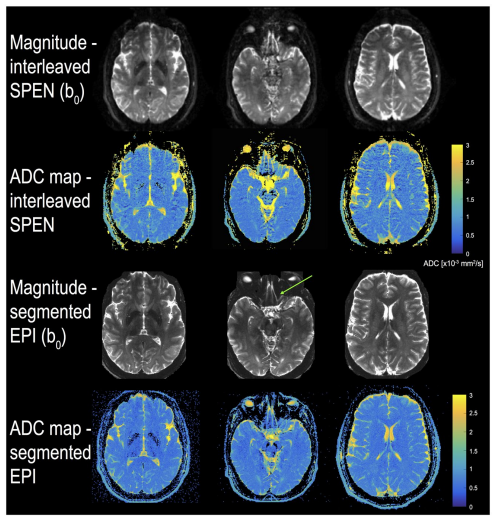

3. High-Accelerated Parallel Imaging With the Inherent Local Feature in PE-xSPEN MRI.png

Dai K, Solomon E, Lee P, Tao G, Qiu Y, Chen H, Frydman L, Zhang Z

Magnetic Resonance in Medicine, 2025